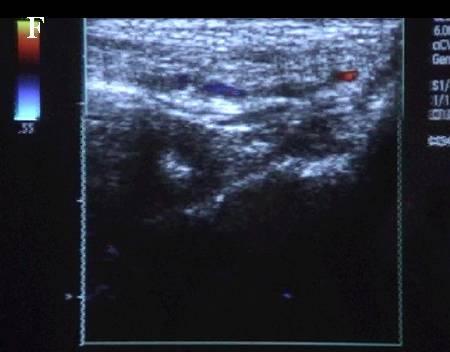

A 连接三联管及穿刺针准备 B 超声引导下注射针进入瘤腔底部(箭头处) C 经注射针注入盐水出现超声频闪现象; D 远端瘤腔内血栓逐渐形成; E 远端、近端瘤腔内血栓完全形成; F 术后足背动脉血流良好. 国内首家开展,例数最多,疗效肯定。此技术在全国推广应用。处于全国领先水平。 |